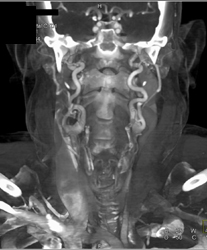

Celiac Artery Aneurysm